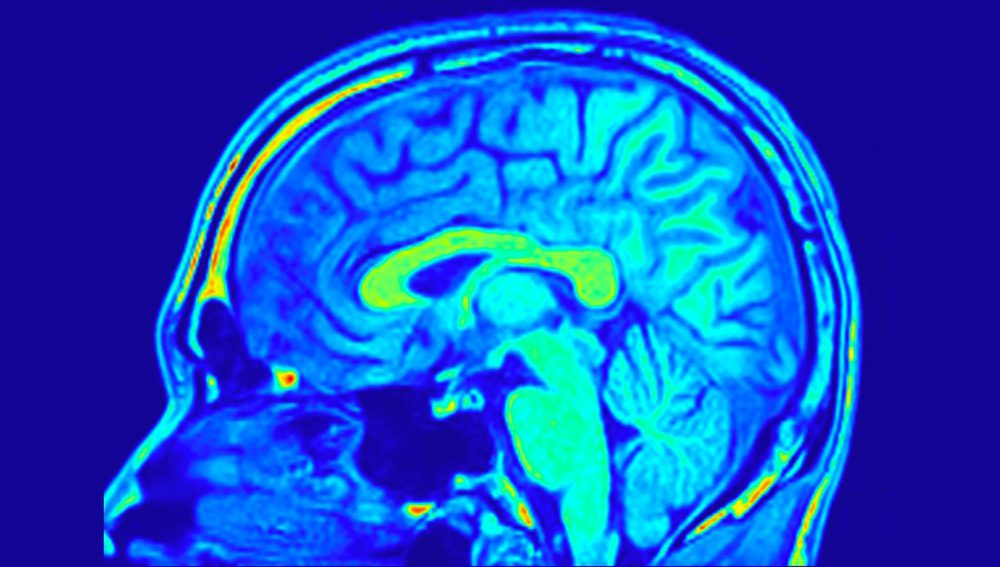

13 ساعة في التصوير بالرنين المغناطيسي

في عامي 2015 و2021، أمضى الأمريكي غير العادي ما يزيد عن 13 ساعة في ماسح التصوير بالرنين المغناطيسي: إما يستريح أو يؤدي مهام الذاكرة. في أحد الاختبارات، طُلب من ديليس أن يتذكر مجموعة من 4 إلى 7 كلمات، تومض كل منها على الشاشة لمدة تزيد قليلاً عن ثانية. لقد طُلب منه أن يحفظها ببساطة عن طريق التكرار.

تمت مقارنة نشاط دماغه مع نشاط اثنين من العلماء الذين عملوا كمجموعة مراقبة: تم تصنيف ذاكرتهم على أنها جيدة جدًا، ولكنها ليست استثنائية.

يتم نشر النتائج على com.bioRxiv. لقد أظهروا أن نشاط دماغ ديليس والمجموعة الضابطة كان متشابهًا أثناء المهمة. كان لدى الثلاثة جميعًا إشارات كهربائية متزايدة في القشرة الخلفية الطحالية، والبصرية خارج الجسم، والقشرة الأمامية الظهرية، وهي مناطق تشارك في الملاحة، والمعالجة البصرية، والذاكرة العاملة، على التوالي.

أدى هذا النهج إلى تنشيط المناطق القشرية الثلاث نفسها، لكنه غير نشاط الحصين، وهو هيكل منحني عميق داخل الدماغ يلعب دورًا رئيسيًا في الذاكرة. في المهمة الأولى، كان نشاط الحصين أعلى أثناء عملية التشفير (أي تلقي معلومات جديدة وربطها بالمعلومات المعروفة) مقارنة بالاستدعاء. وفي الثانية تغيرت الصورة إلى العكس. بالإضافة إلى ذلك، في المهمة مع البطاقات التي قمنا بتنشيطها النوى المذنبة – الهياكل على شكل حرف C لا تشارك فقط في الذاكرة، ولكن أيضًا في التعلم. افترض الباحثون أن مشاركة النوى المذنبة تحول الذاكرة إلى “مهارة مستقرة”.

تمت مقارنة نشاط دماغ صاحب الرقم القياسي ببيانات من 887 مشاركًا في مشروع Human Connectome. اتضح أن لديه معدل اتصال وظيفي أعلى بكثير – أي أن مناطق مختلفة من دماغه تنسق عملها بشكل أكثر كفاءة، مما يدل على تفاعلها المنسق جيدًا.